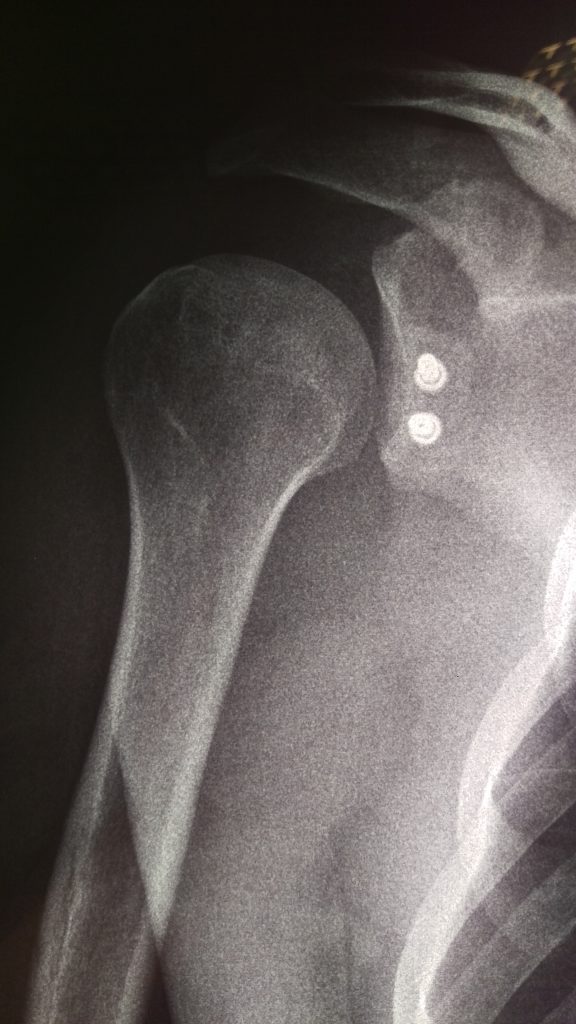

После Latаrjet, первая перевязка

image

После Latаrjet, рентгеновский контроль — положение костного блока идеальное